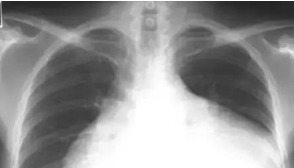

后来决定运动锻炼降压,于是开始撸铁,开始长跑,按理说运动应该利于血压正常呀?可是最近霍先生一动就穿,晚上躺不下,一躺下就憋气;今天我一问我就说八九不离十心衰了,他还不信,结果一做心脏彩超:高血压性心脏病,心功能EF35?正常人应该高于55?这属于严重的心衰,不得不收住院进一步诊治。心衰简单立即就是心脏病中的癌症,5年死亡率和肺癌一样,住院死亡率6?您说霍先生这么年轻,就心衰了,以后怎么办?那么高血压最怕什么运动?第一、血压高没有降到安全水平就运动

高血压鼓励运动,没错。运动在一定程度上确实能够降压,甚至对于轻度高血压来说,运动能替代降压药。可是并不是所有的高血压都鼓励运动,或者说都鼓励马上运动。如果血压高于160/100,那么肯定不建议马上运动,必须通过降压药先把血压降到160/100以下,同时没有头疼头晕等等症状的前提下才建议运动。而不是像霍先生血压都180/110了,都是3级高血压了,还去通过运动来降压,那血压能降下来吗?第二、合并疾病,不吃药,只运动如果发现高血压的同时,已经合并了糖尿病,或心血管疾病,比如冠心病、心绞痛、心衰、脑梗死;肾病等等问题;那么也不建议马上运动,必须先把血压降到130/80以下;再根据个人情况,评估其他疾病后,决定能不能运动。就拿霍先生说,他自己1年前发现高血压,可能那时候心脏已经扩大了;这时候必须马上降压,需要做个彩超看看有没有心脏扩大,如果有心脏扩大,还得治疗心衰。如果那样就不会像现在这么严重,心功能只有35?可是霍先生只知其一不知其二,只知道运动能降压,根本不知道不是所有高血压,都必须马上运动降压,像他本身血压高,不建议马上运动,且可可能已经合并心脏扩大,那么这时候运动,无疑雪上加霜,加之的心衰进程。第三、无氧运动为主